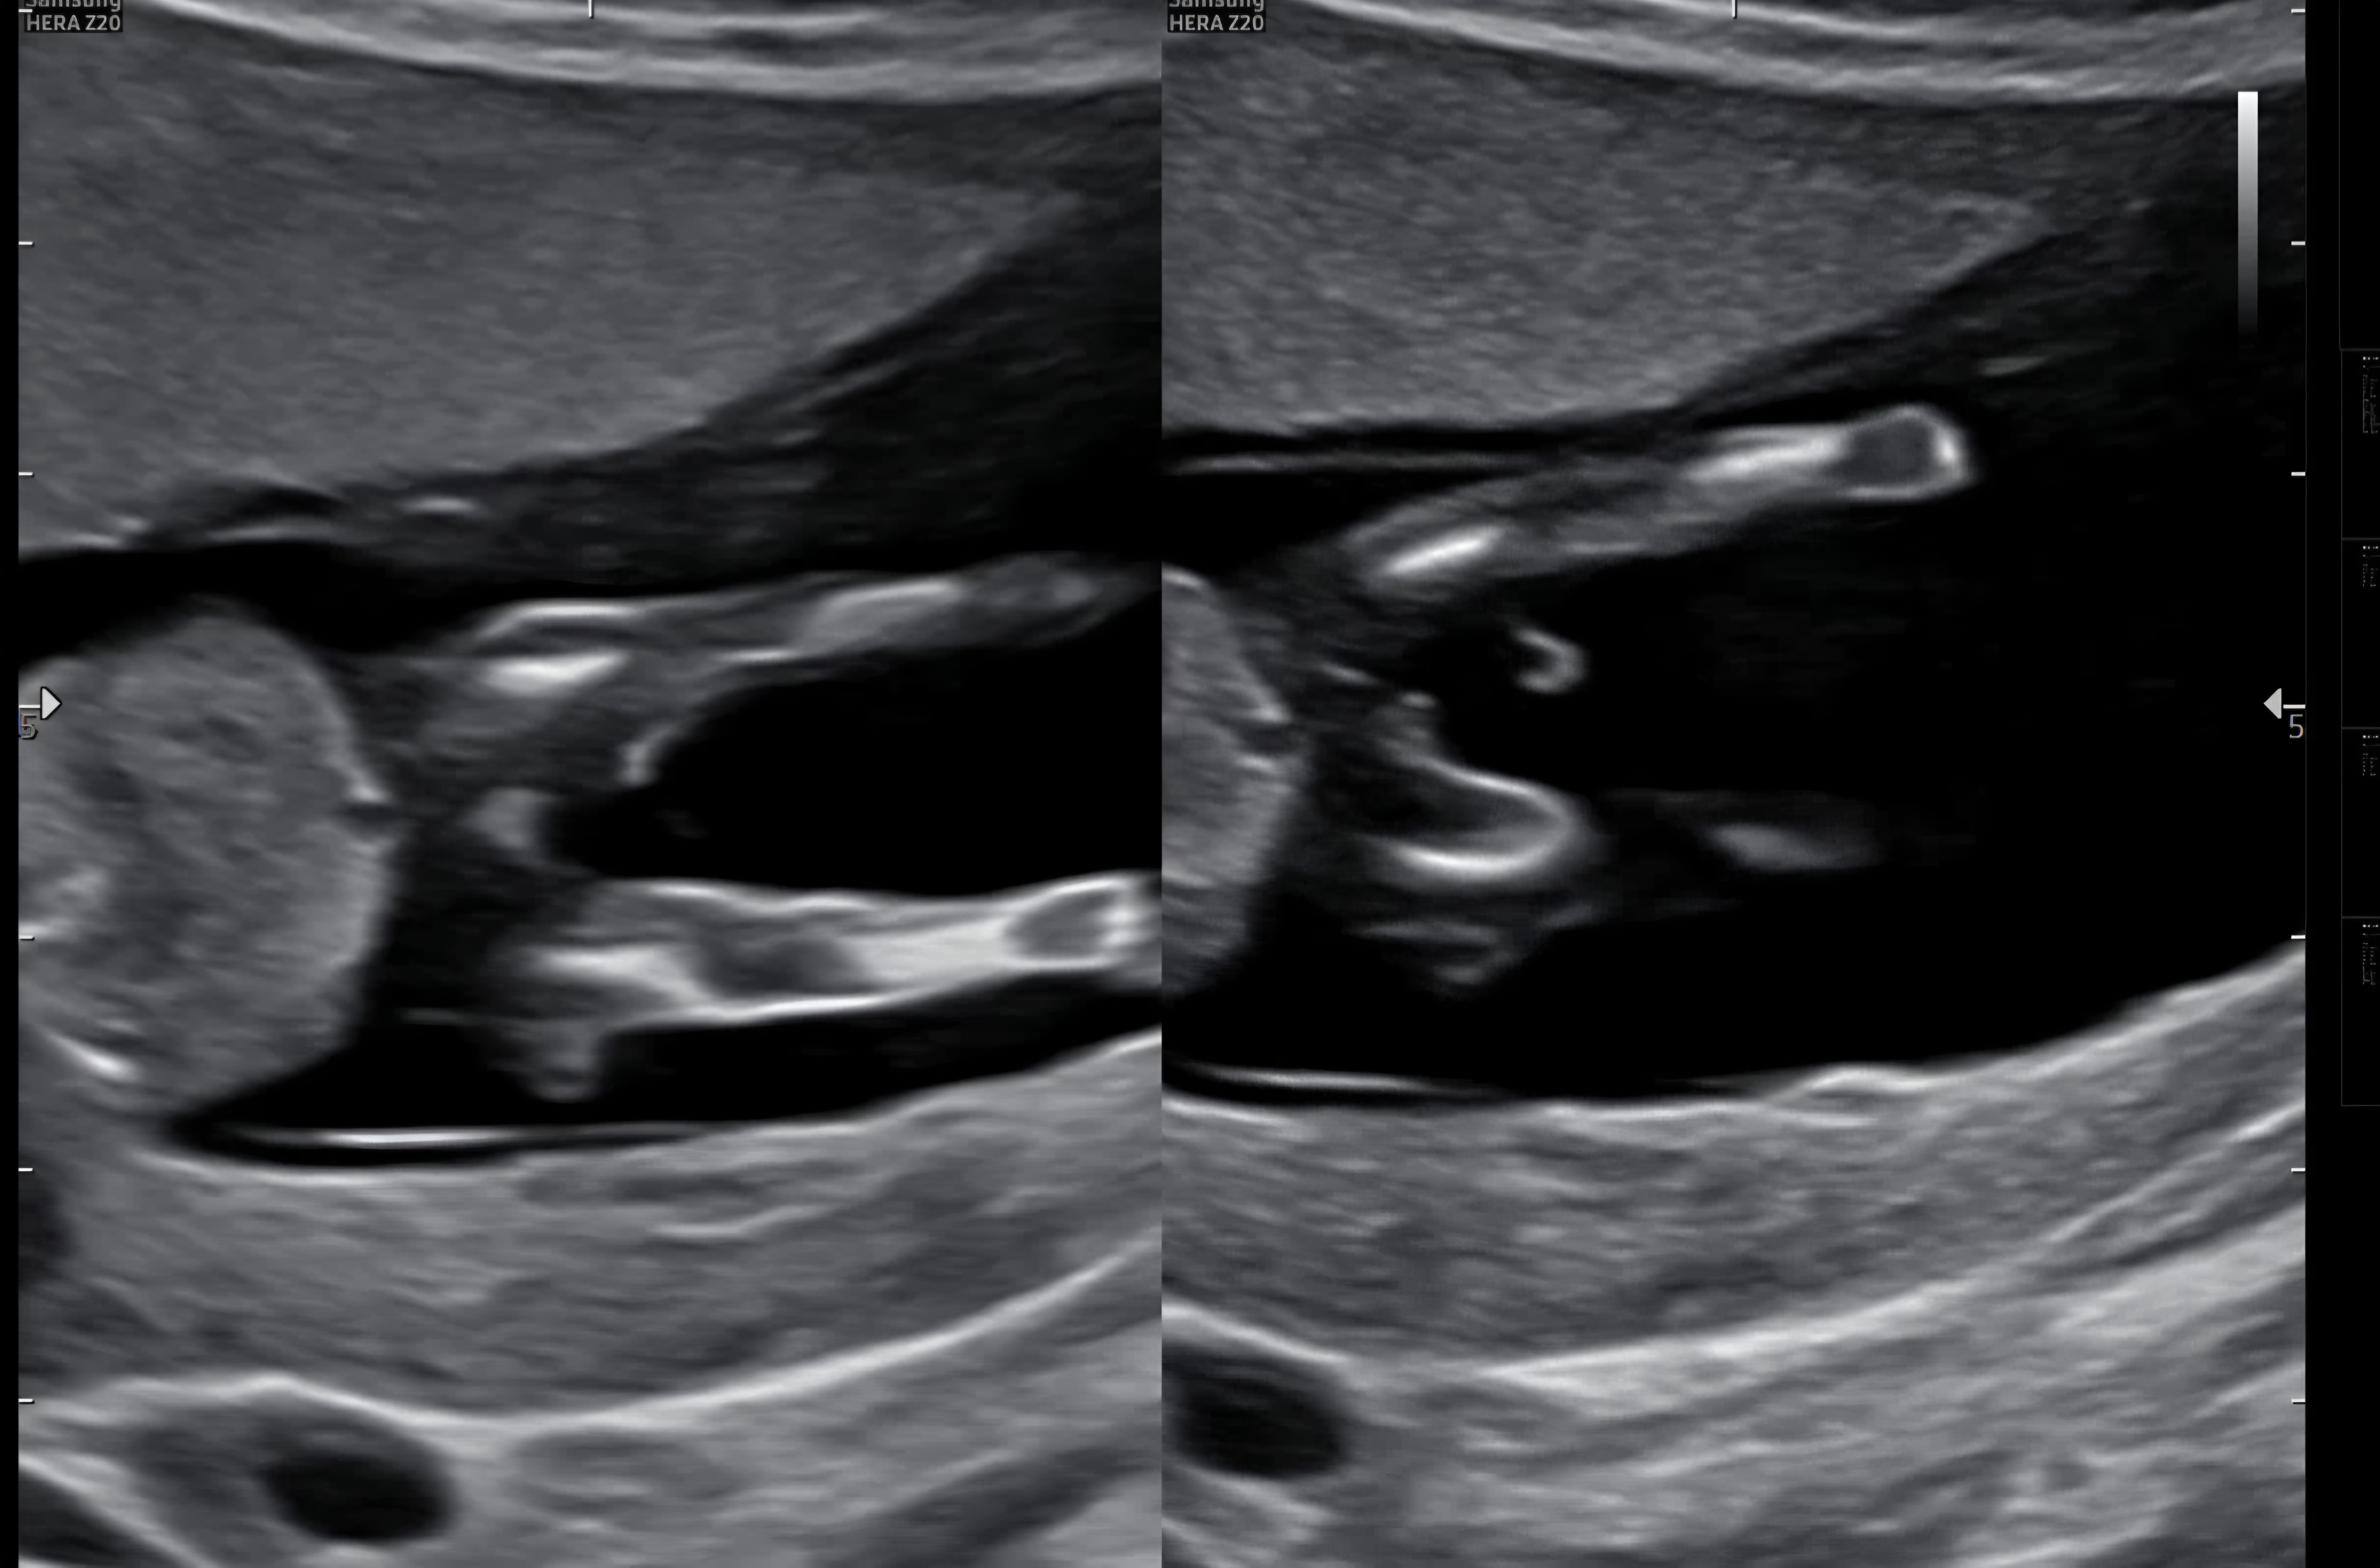

12주 6일 다리사이 성별봐주세요!

제 눈에는 아직 안보이는 것 같은데 좀 더 기다려야할까요? 의사쌤이 우측 사진 다리사이에서 살짝 떨어진 하얀색?은 탯줄이래요.. 성별 아직 아예 언급이 없으시니요ㅠ